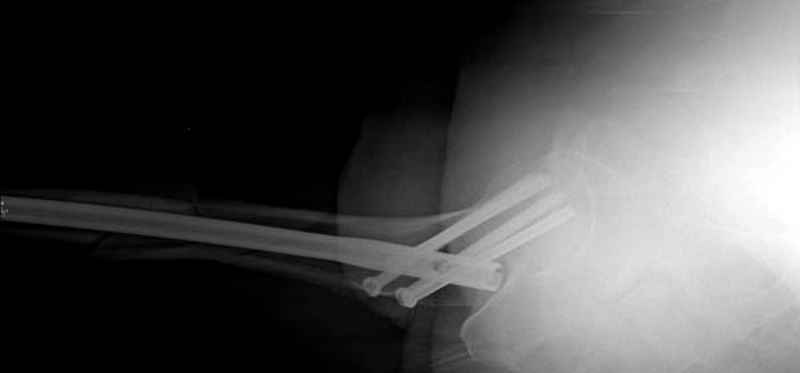

Учитывая, что случай ургентный, больной поступил вечером, не стали делать вытяжение и срочно провели операцию по фиксации перелома бедра антеградным штифтом Versa Nail от DePuy.

Для профилактики дальнейшего раскола в шейке предварительно во время проксимального рассверливания спереди и сзади провели временные спицы, которые в дальнейшем были заменены на шурупы (miss nail method)

Обычная спасательная фасциотомия для обычного больного в этом случае было бы приговором, поэтому несмотря на высокие цифры компартментального мониторинга больного оставили под наблюдением с обкладкой конечности льдом.

Кровотечение удалось контролировать, и больной через пару дней выписан на амбулаторное лечение.